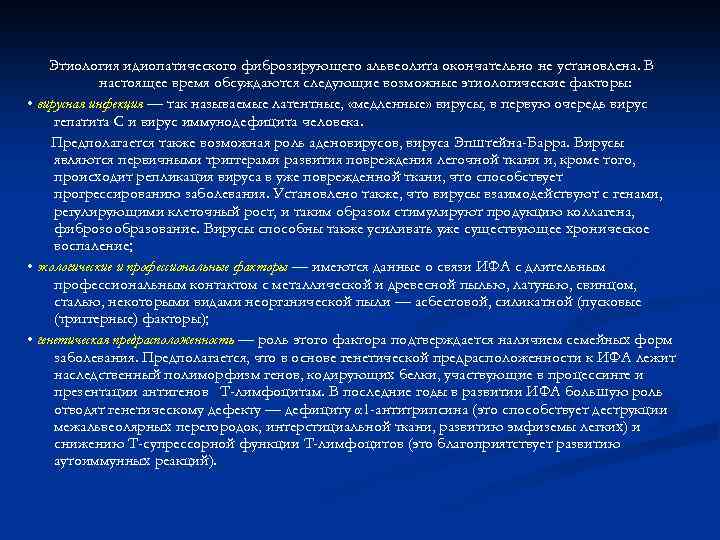

Этиология идиопатического фиброзирующего альвеолита окончательно не установлена. В настоящее время обсуждаются следующие возможные этиологические факторы: • вирусная инфекция — так называемые латентные, «медленные» вирусы, в первую очередь вирус гепатита С и вирус иммунодефицита человека. Предполагается также возможная роль аденовирусов, вируса Эпштейна-Барра. Вирусы являются первичными триггерами развития повреждения легочной ткани и, кроме того, происходит репликация вируса в уже поврежденной ткани, что способствует прогрессированию заболевания. Установлено также, что вирусы взаимодействуют с генами, регулирующими клеточный рост, и таким образом стимулируют продукцию коллагена, фиброзообразование. Вирусы способны также усиливать уже существующее хроническое воспаление; • экологические и профессиональные факторы — имеются данные о связи ИФА с длительным профессиональным контактом с металлической и древесной пылью, латунью, свинцом, сталью, некоторыми видами неорганической пыли — асбестовой, силикатной (пусковые (триггерные) факторы); • генетическая предрасположенность — роль этого фактора подтверждается наличием семейных форм заболевания. Предполагается, что в основе генетической предрасположенности к ИФА лежит наследственный полиморфизм генов, кодирующих белки, участвующие в процессинге и презентации антигенов Т-лимфоцитам. В последние годы в развитии ИФА большую роль отводят генетическому дефекту — дефициту α 1 -антитрипсина (это способствует деструкции межальвеолярных перегородок, интерстициальной ткани, развитию эмфиземы легких) и снижению Т-супрессорной функции Т-лимфоцитов (это благоприятствует развитию аутоиммунных реакций).